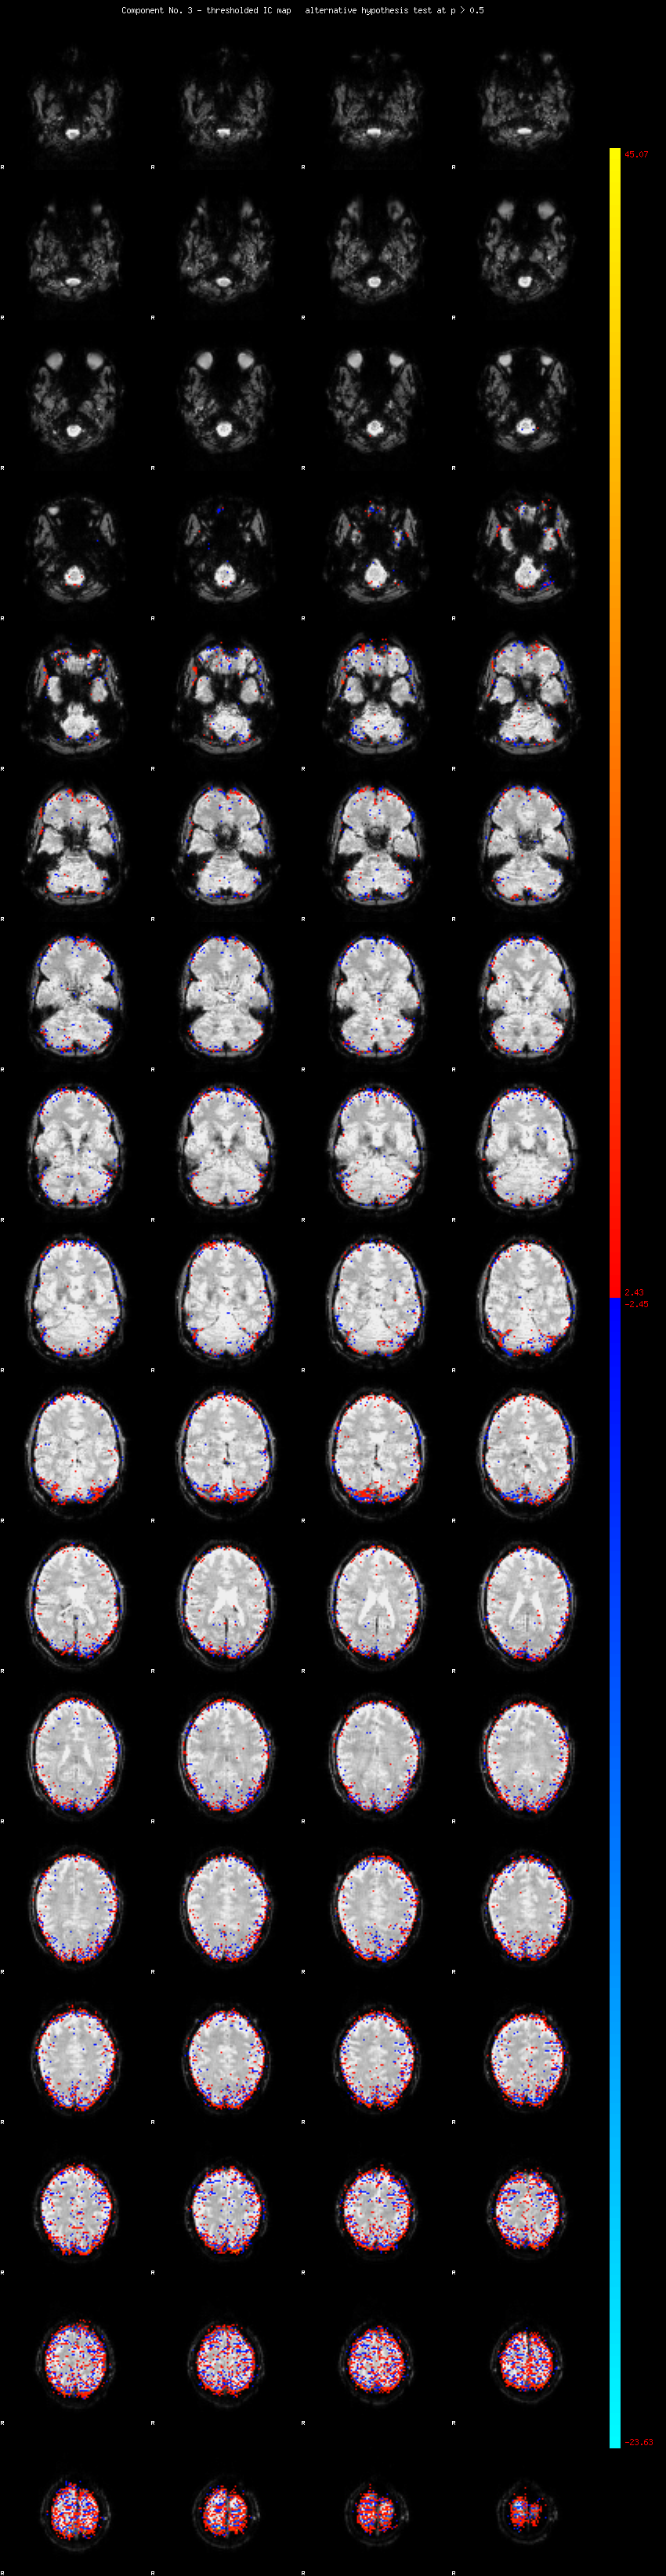

MELODIC Component 3

2.82 % of explained variance;     1.87 % of total variance